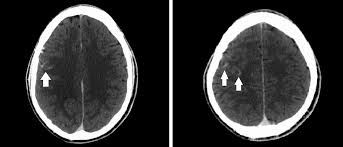

Subaraknoid kanama (SAK) akut başlangıçlı, ani ve şiddetli baş ağrısı ile ortaya çıkan klinik bir durumdur. Baş ağrısına ilaveten ciddi bulantı, kusma, baş dönmesi, konfüzyon, ajitasyon, fokal nörolojik defisitler ve kan basıncı yüksekliği görülebilir. Kanamadan 6-24 saat sonra meningeal irritasyon bulguları bu klinik duruma eklenebilir.